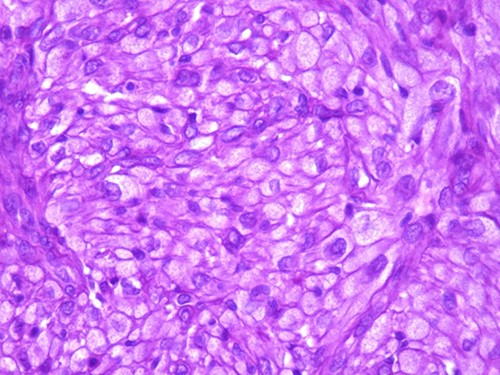

A 42-year-old man with no clinical history presented with a non-ulcerated polypoid skin nodule of the front side of the chest wall, which had grown over a period of 6 months, measuring 1,8 × 1,5 cm (Fig. 1). The lesion was removed completely with tumor-free margins of 0,5 cm. Microscopically, the tumor was composed of a diffuse infiltrate of polygonal cells with abundant granular cytoplasm and vesicular nuclei (Figs 2 and 3). There was no atypia or necrosis. The average mitotic count was one to two per 10 high-power field. Immunohistochemistry showed positive expression for CD10, CD68 and ALK with negative staining for CK AE1/AE3, CD34, S100 and HMB45 (Figs 4 and 5). No recurrence was noted during follow-up of 6 months.

The tumor is composed of epithelioid cells with abundant granular cytoplasm and vesicular nuclei (magnification at ×400).

Microscopically, DNNGCT are well circumscribed and composed of large spindled or polygonal to epithelioid cells with abundant granular cytoplasm [2, 4, 5]. The nuclei are vesicular with a single prominent nucleolus [7]. The mitotic index varies from 1 to 9 per 10 high-power field. A subset of this tumor show atypical cytologic features including nuclear pleomorphism and increased mitoses [1, 2, 4]. These histological features do not seem to correlate with a worse clinical behavior [1, 2, 4].